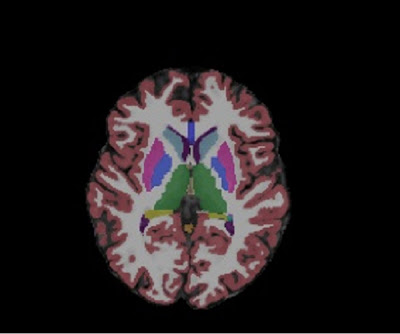

Finally, I’d like to focus on brain structures that are located deep in the brain, highly connected to the rest of the brain and supporting/regulating different key functions. These areas are more generally defined as subcortical areas, but we can also specify different subcortical systems.The basal ganglia are a group of connected nuclei forming a continuum at the base of the brain.

• caudate nucleus

• putamen: works together with the caudate, and they are called striatum

• globus pallidus: also works together with the putamen, and they are called lentiform nucelus

• subthalamic nucleus and substantia nigra: more distant from the other nuclei but functionally related to them for motor control.

Functionally, the basal ganglia play an important role in motor control, motivation, reward-based learning, and addiction. Damage to these areas can lead to serious motor and cognitive deficits. An example? Motor alterations characteristic of Parkinson’s or Huntington’s disease.